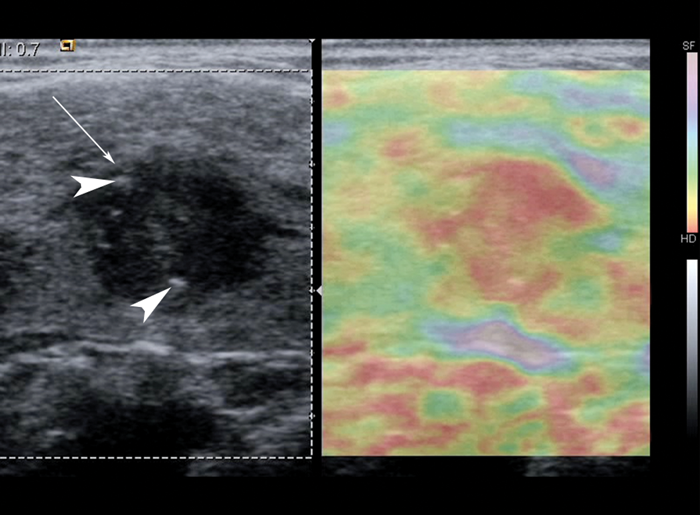

Since 2005, over 50 pilot studies of strain elastography and a handful of shear wave elastography studies have evaluated the accuracy of USE for thyroid malignancy [2, 4-10]. These have differed considerably in terms of sample size (mean ~100 nodules, range 16-912), patient and nodule inclusion / exclusion criteria, USE technology, practical technique, nodule scoring system and reference standards used. Approximately 90% of malignancies in these studies are papillary thyroid carcinomas, thus published accuracy results probably pertain to this malignant histology. Encouragingly, most studies document strain and shear wave indices equating to higher stiffness in malignant compared to benign nodules (Figures 1-2). For strain elastography, a recent meta-analysis of 5481 thyroid nodules from 31 studies calculated a pooled 79% sensitivity and 77% specificity for malignancy using qualitative assessment, and 85% sensitivity and 80% specificity using strain ratios [4]. Promising results are also emerging for shear wave elastography [6, 9]. For example, in a study of 297 nodules, Veyrieres et al. found a cut off of >66kPa achieved 80% sensitivity and 90.5% specificity for malignancy [9]. Importantly, combining USE with grayscale US features achieved 97% sensitivity and 99.5% negative predictive value.

Figure 1: Grayscale US image with corresponding strain elastogram of a hypoechoic nodule (arrow) containing focal punctate calcifications (arrowheads), histologically confirmed as papillary thyroid carcinoma. The elastogram colour scale ranges from purple to red, indicating relatively soft to hard respectively. The nodule appears mostly red on USE, which suggests a relatively stiff nodule. Note that strain elastography displays relative strain, so this method requires the presence of normal tissue in the elastogram for reference.